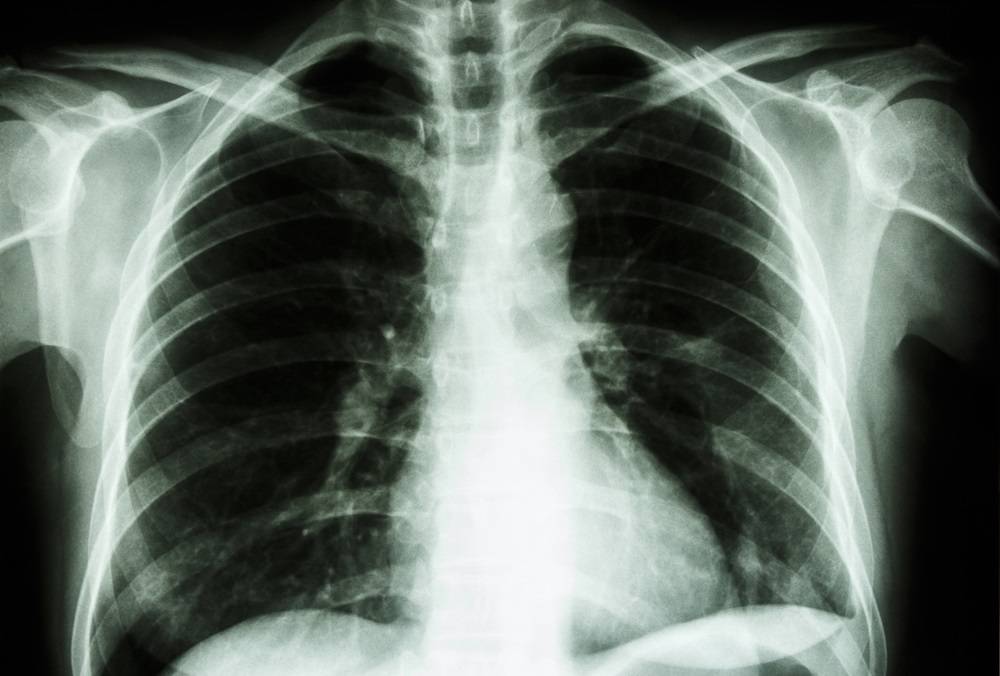

Bronhopneumopatia obstructivă cronică este o boală diversă, care variază de la bronșită până la emfizem pulmonar, caracterizată prin simptome respiratorii persistente și prin limitarea fluxului de aer care se datorează căilor respiratorii și /sau anomaliilor alveolare. La nivel mondial, cel mai des întâlnit factor de risc este fumatul, însă boala poate fi cauzată și de expunerea îndelungată la pulberile industriale, noxele chimice, fumul produs de arderea combustibililor biologici (cărbune, lemn, gunoi de grajd). Experții preconizează că, în mai puțin de trei ani, BPOC va deveni a treia cauză de deces din lume, depășind alte afecțiuni precum diabetul zaharat sau hipertensiunea arterială.

Primele semne care impun vizita la un medic pneumolog sunt tusea cronică, producția cronică de spută (flegmă), șuieratul, gâfâitul, senzația de sufocare (dispnee) instalată cel mai adesea brusc, pe fondul unei oboseli accentuate sau toleranța la efort care devine din ce în ce mai redusă.